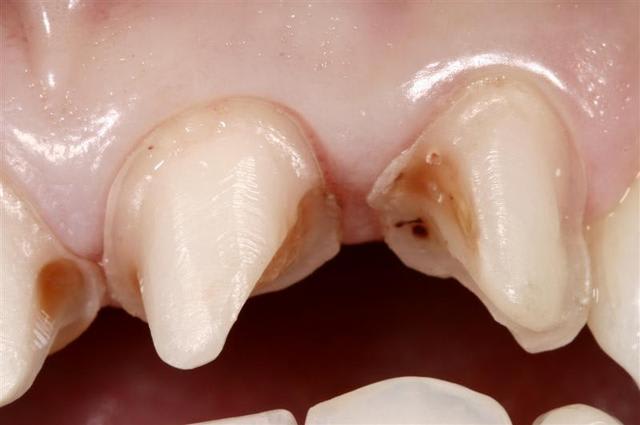

Reste un peu de colle :)

Il y a eu blanchiment

Pour info les compo avaient des vis intra dentinaire.. Encore un qui croyait pas dans le collage..